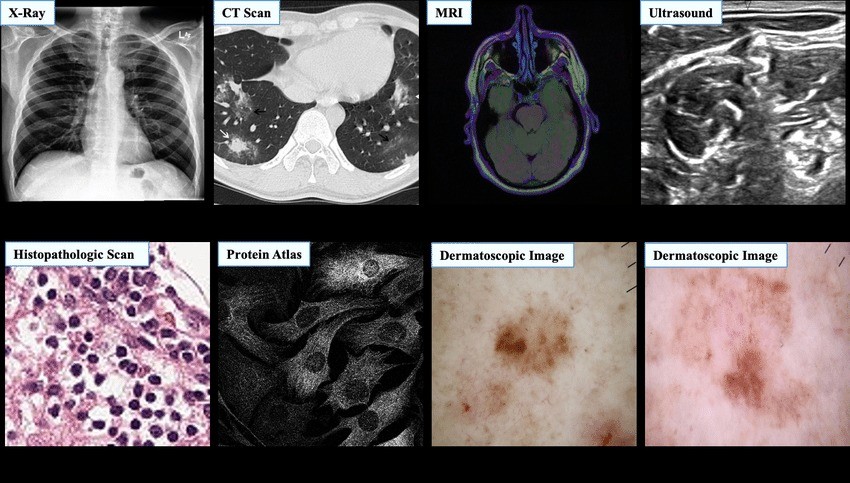

Medical images. Medicine has been revolutionized by the multiplicity of imaging acquisition devices currently available. X-rays, CT scans, MRIs, OCTs, ultrasound images, etc., are used on a daily basis for clinicians and radiologists to provide diagnosis, plan treatments, and monitor diseases. Depending on the imaging modality, this data can be 2D or 3D and sometimes includes a time dimension to capture motion, such as Cine MRIs. Automatically processing this data is a subfield of machine learning known as Computer Vision, and is challenging in itself due to the complexity and dimensionality of images. Common applications of AI in medical imaging include detecting and classifying abnormalities, assisting radiologists with diagnosis, and quantifying features from organs or lesions, among others.